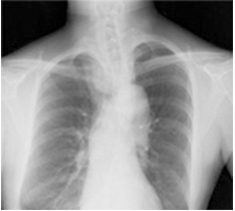

Temporal Subtraction処理は、独自のアルゴリズム補正をもとに、胸部画像の現在と過去の差分画像を生成する画像処理技術です。

がん予防重点健康教育及び、がん検診実施のための指針では、胸部エックス線写真の読影方法として二重読影の結果必要と判断される場合は、比較読影を行うことが示されています。*

しかし、画像を細かな部分まで見比べるには時間がかかり、また、小さな変化は見逃してしまう可能性があります。

そこで、現在と過去の差分画像を生成し「変化の有無」を可視化することで、診断精度の向上と時間短縮が期待でき、胸部読影を強力にサポートします。